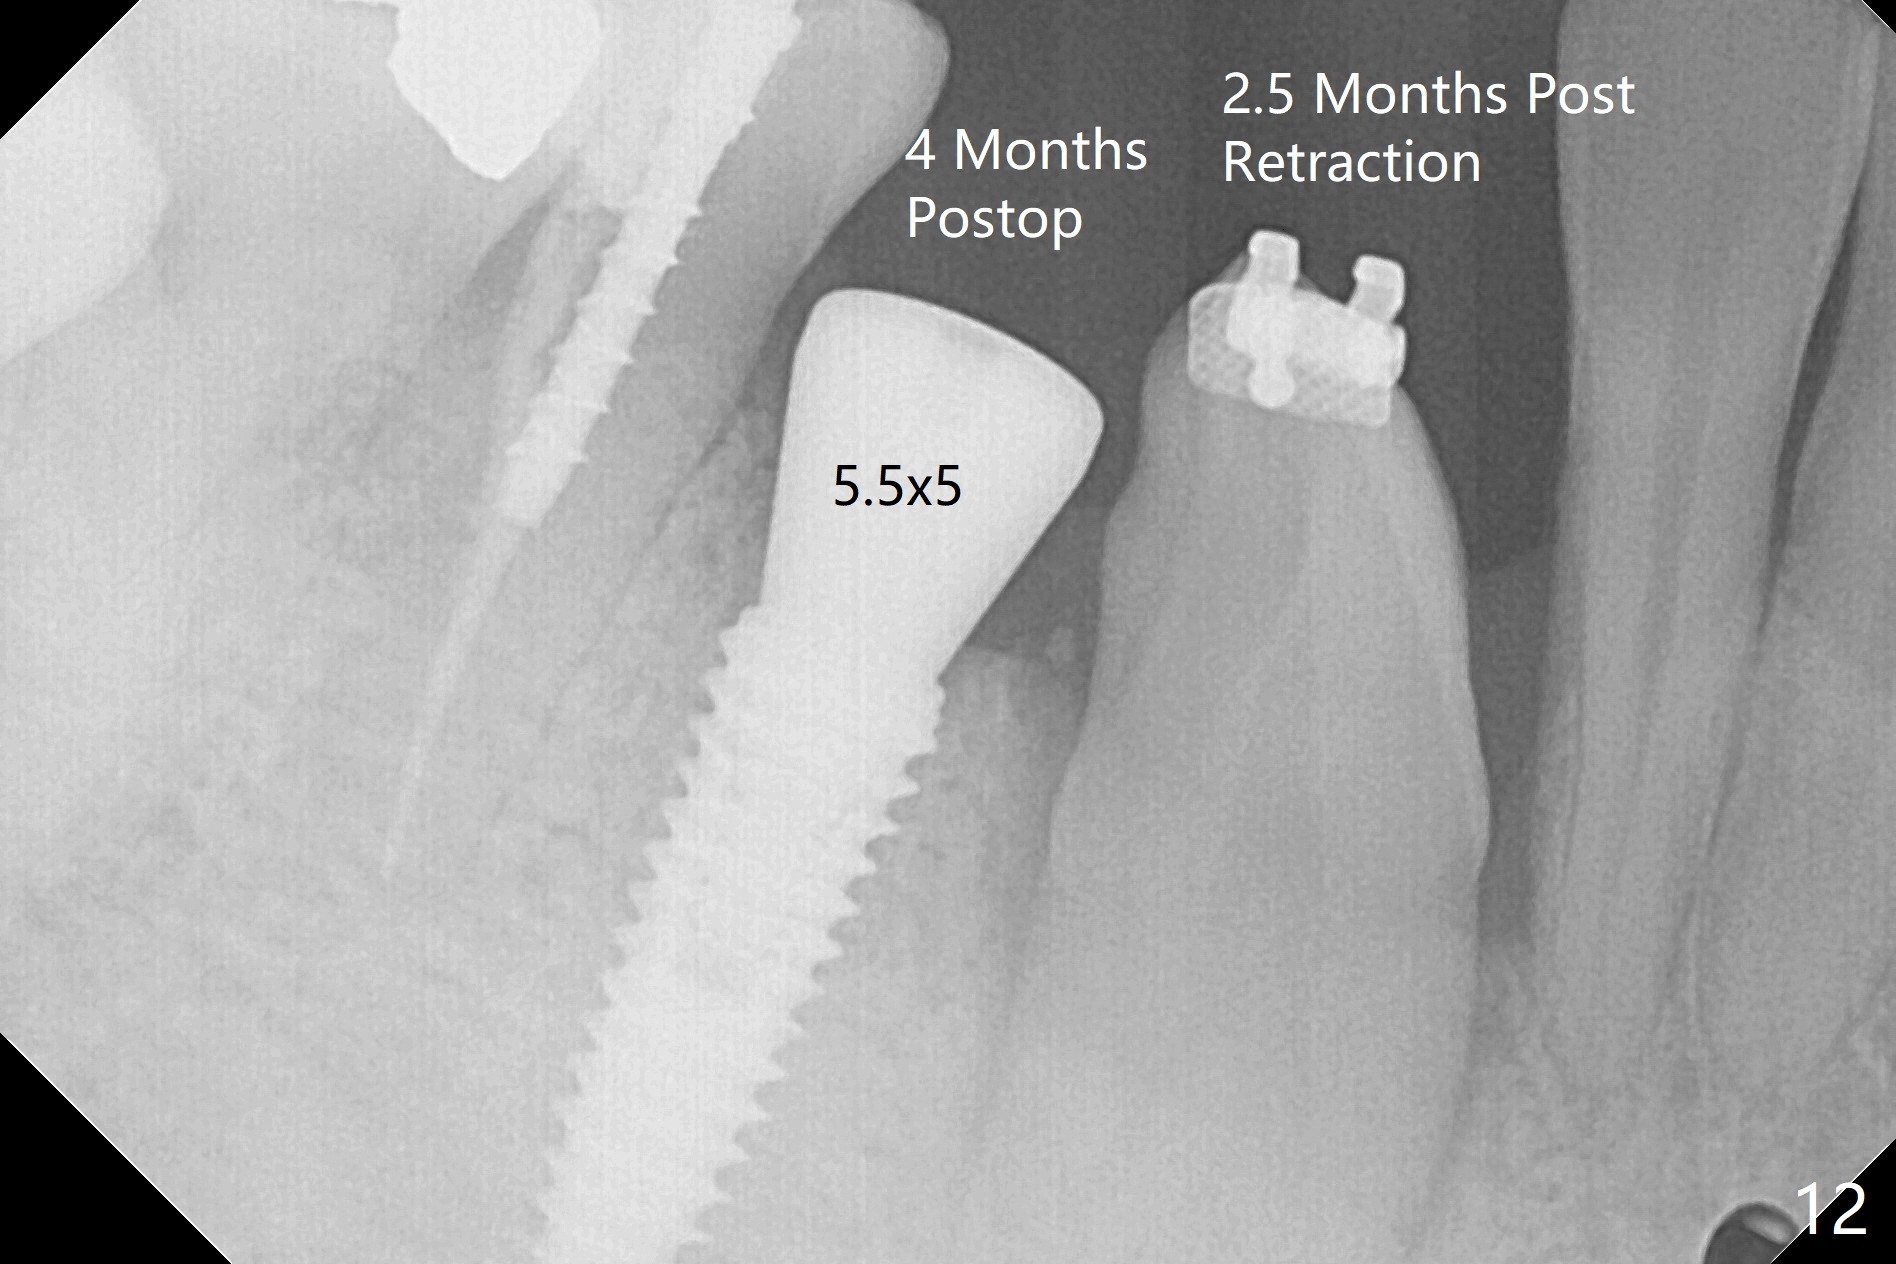

When the surgical guide for #28 is removed, the 4x13 mm implant is found to be superficial and buccal. Part of the buccal mucosa is nonkeratinized. After 1 mm deeper placement of the implant, CT confirms the buccal placement (Fig.1, as compared to design). In fact the guide was doubly checked for fitness prior to osteotomy, but grossly it seemed to be seated properly. The suspicion is related to the trimming at the site of #27 (Fig.2,3 (*), as compared to a mounted model in Fig.4,5 (arrowhead) and the model sent to lab for guide fabrication). The lab agrees to redesign the case. There is a narrow buccal band 1 week postop (Fig.6). The patient is a smoker. The implant was placed buccal (Fig.7, 1 month postop). A new 4x13 mm implant is placed on the top of the 1st line following 3x14.5 mm drill (Fig.8 (35 Ncm)). In fact the implant position is not changed much. Four months post banding (20 ss) and 2 months post 2nd implant placement, the tooth #27 is exposed for bracket; extrusion is initiated (Fig.9). In 3 weeks of retraction, the bracket is supragingival (Fig.10). The canine contacts the distal healing abutment with 2 months of retraction (Fig.11). It seems necessary to initiate lower bracket placement. There is no bone loss 4 months postop (Fig.12). A 4.5x7(4) mm abutment is placed (Fig.13) for a temporary crown as an anchor (Fig.14) to further extrude #27 with continuous inter-arch retraction (to reduce tension upon #26 with severe bone loss (Fig.12)). LR3 extrusion is incomplete, although there is an increase in bone distal to LR2 ~ 10 months of extrusion (Fig.15).